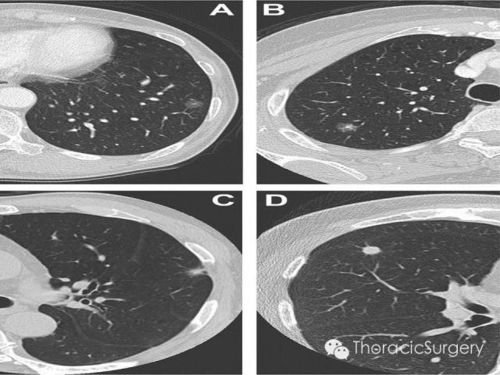

在体表肿块、肝脏或肺部肿瘤的情境下,穿刺活检如同超声或CT的导航,准确获取肿瘤组织。其准确率高达95%以上。每一种方法都有其局限性。当穿刺存在高风险,如肿瘤位置特殊时,我们会考虑采用其他策略。这时,胸腔积液脱落细胞学检查、手术切除标本或是通过粪便基因检测如SDC2甲基化检测等替代方法就显得尤为重要。